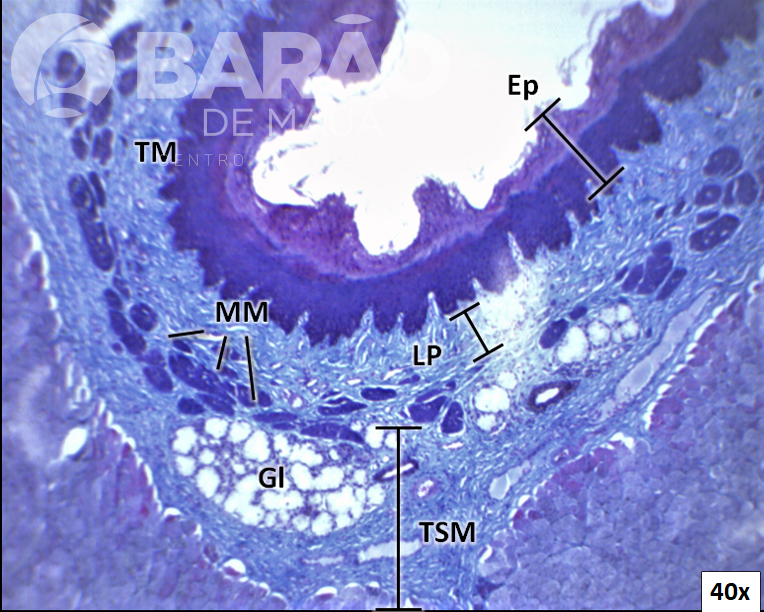

Duodeno - Ep = epitélio, MB = M. de Brucke, GlI = glândulas de Lieberkuhn “intestinais”, MM = muscular da mucosa, GlB = glândulas de Brunner “duodenais”, Linha tracejada = limite entre a base das vilosidades e as glândulas intestinais - Coloração: H&E

Duodeno - Ep = epitélio, MB = M. de Brucke, GlI = glândulas de Lieberkuhn “intestinais”, MM = muscular da mucosa, GlB = glândulas de Brunner “duodenais”, Linha tracejada = limite entre a base das vilosidades e as glândulas intestinais - Coloração: H&E.